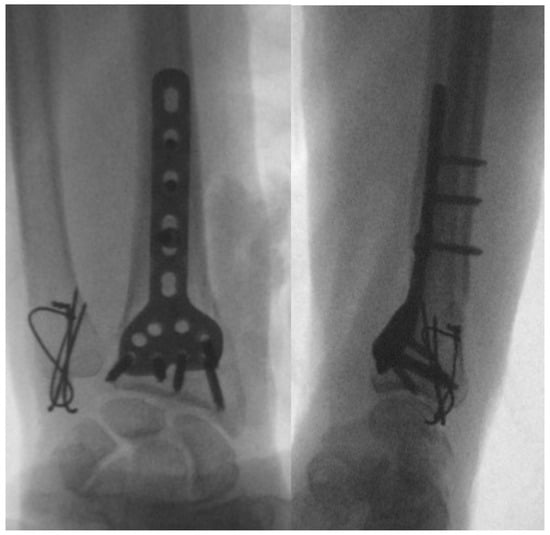

Treatment typically involves surgical intervention, such as open reduction and internal fixation (ORIF) and DRUJ stabilization (Figure 7) [7,65,66]. Postoperative care includes immobilization and rehabilitation, depending on DRUJ stability [62,65,67]. Complications can include pain, stiffness, instability, malunion, nonunion, and rare neurovascular damage [58,61,62].

Figure 7. ORIF of a Galeazzi fracture via the Henry approach using a titanium plate.

Prompt and appropriate treatment, often involving surgery, is crucial for optimal outcomes and preventing long-term complications. A multidisciplinary approach involving orthopedic specialists and radiologists is essential for comprehensive care and recovery [7,61,62,68].